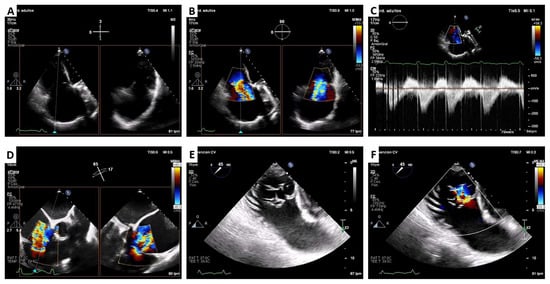

2. Cardiovalve Cases

3. Lux-Valve Plus Case